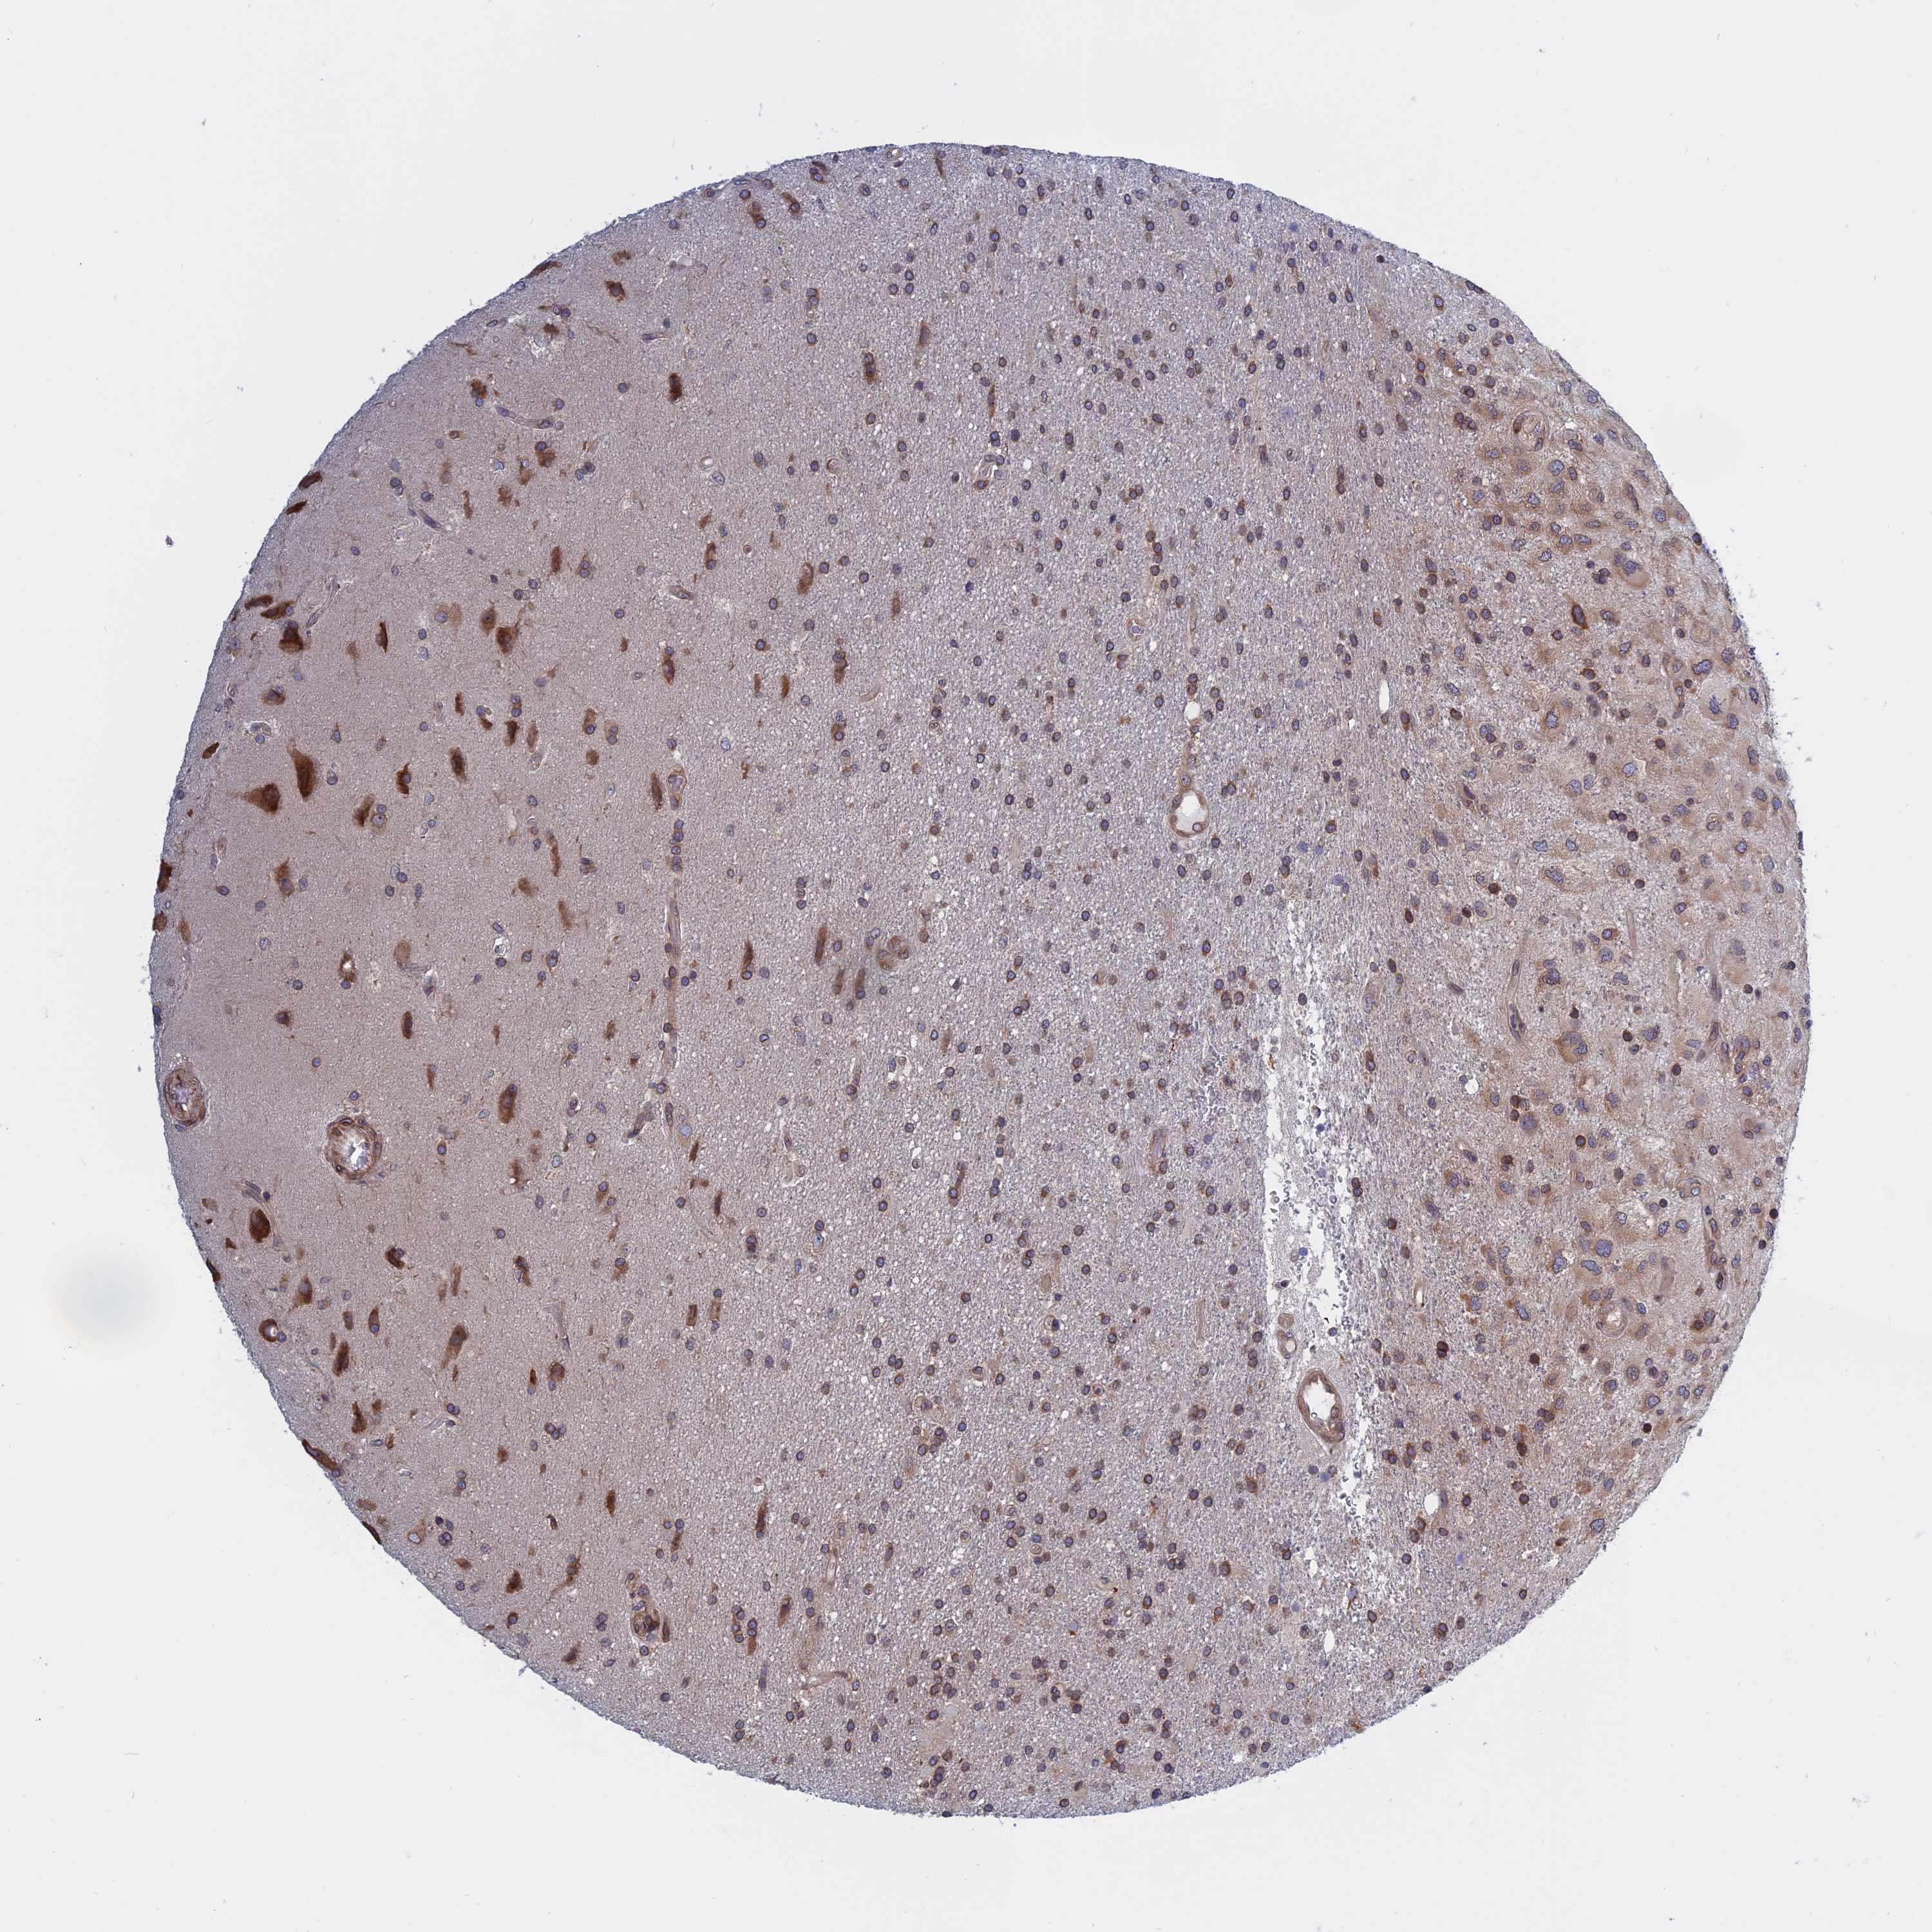

GLIOMA - Protein expressioni

A mouse-over function shows sample information and annotation data. Click on an image to view it in a full screen mode. Samples can be filtered based on level of antibody staining by selecting one or several of the following categories: high, medium, low and not detected. The assay and annotation is described here.

Note that samples used for immunohistochemistry by the Human Protein Atlas do not correspond to samples in the TCGA dataset.

Antibody stainingi

Antibody staining in the annotated cell types in the current human tissue is reported as not detected, low, medium, or high, based on conventional immunohistochemistry profiling in selected tissues. This score is based on the combination of the staining intensity and fraction of stained cells.

Each image is clickable and will lead to virtual microscopy that enables deeper exploration of all samples and also displays staining intensity scores, fraction scores and subcellular localization as well as patient and tissue information for each sample.

Antibody HPA030711

Antibody CAB006269

Staining

High

Medium

Low

Not detected

Intensity

Strong

Moderate

Weak

Negative

Quantity

>75%

75%-25%

<25%

None

Location

Nuclear

Cytoplasmic/membranous

Cytoplasmic/membranous,nuclear

Glioma, malignant, High grade

Glioma, malignant, Low grade